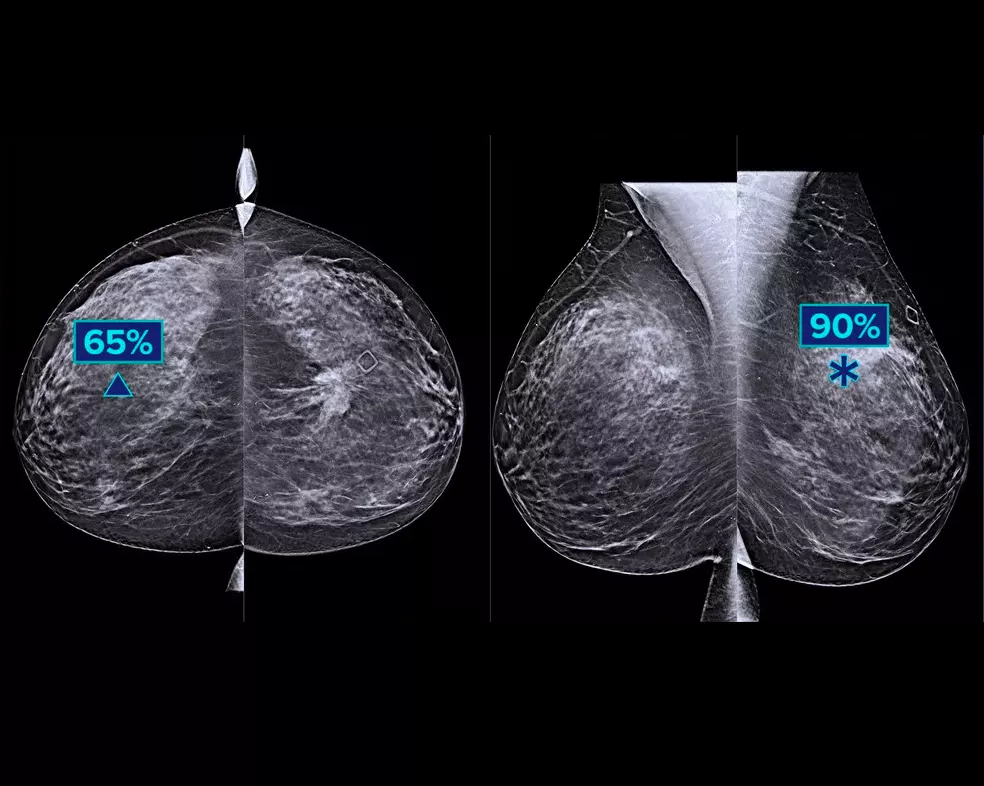

A deep-learning algorithm designed to aid radiologists' diagnostic performance and detect breast cancer1-3 from tomosynthesis images obtained using the Hologic Dimensions Mammography® Systems. The algorithm locates lesions that are likely to represent breast cancer by searching each slice of the tomosynthesis image set. The suspicious areas are highlighted for concurrent reading at the radiologist's workstation to aid in interpretation.

Study shows +9% improvement in observed reader sensitivity for cancer cases.1.2 Works on standard and high-resolution tomosynthesis images; overlay on 3DQuorum SmartSlices and synthesised 2D images.

Tools for Easy Lesion Identification

The algorithm looks for 3 main groups of suspicious lesions: calcifications, masses, densities and distortions, and any combination of these lesions. Outputs may vary on different reading workstations.